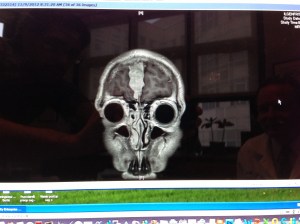

By this time tomorrow the parasaggital meningioma resting behind my skull will have been removed. I am scheduled for operation tomorrow at noon, and I am working right now to make sure that I am properly prepared mentally, physically, spiritually, and otherwise.

I’ve been asking myself how best to prepare for something like this, and I’ve been eager to start sharing thoughts here. With no clear idea where to start, I turned to these images. I have so much to say about these images and this topic, but for the moment I want to let the visuals speak for themselves.